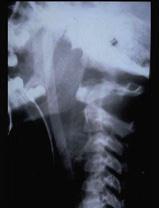

诊断寰枢关节脱位时,颈椎正侧位平片测量寰齿间距应大于 ( )A、5mmB、6mmC、3mmD、4mmE、2mm

问题 诊断寰枢关节脱位时,颈椎正侧位平片测量寰齿间距应大于 ( )

选项 A、5mm B、6mm C、3mm D、4mm E、2mm

答案 C